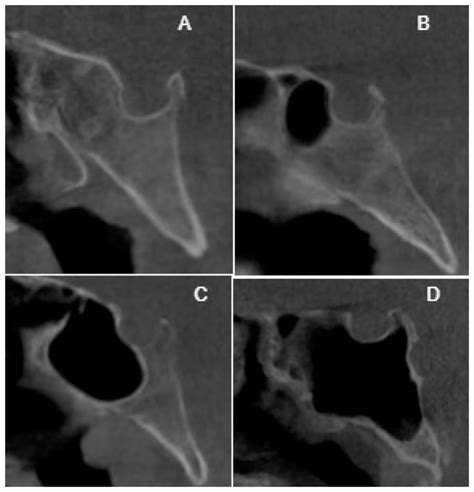

Computed Tomography (CT)

CT scans provide detailed images of the bony structures of the skull, making them ideal for evaluating fractures or bony tumors involving the lesser wing of sphenoid. CT scans can also help identify any displacement or narrowing of the optic canal or superior orbital fissure.

Radiological Anatomy of the Lesser Wing of Sphenoid

Understanding the radiological anatomy of the lesser wing of sphenoid is crucial for accurate diagnosis and treatment planning. The following table summarizes the key radiological features of the lesser wing of sphenoid:

Structure Radiological Features

Optic Canal Bony canal transmitting the optic nerve and ophthalmic artery. Visible on CT and MRI.

Superior Orbital Fissure Gap between the lesser and greater wings of the sphenoid bone. Visible on CT and MRI.

Lesser Wing of Sphenoid Thin, flat structure forming part of the anterior cranial fossa and the roof of the orbit. Visible on CT and MRI.

These radiological features are essential for evaluating the lesser wing of sphenoid and its associated structures in various clinical scenarios.